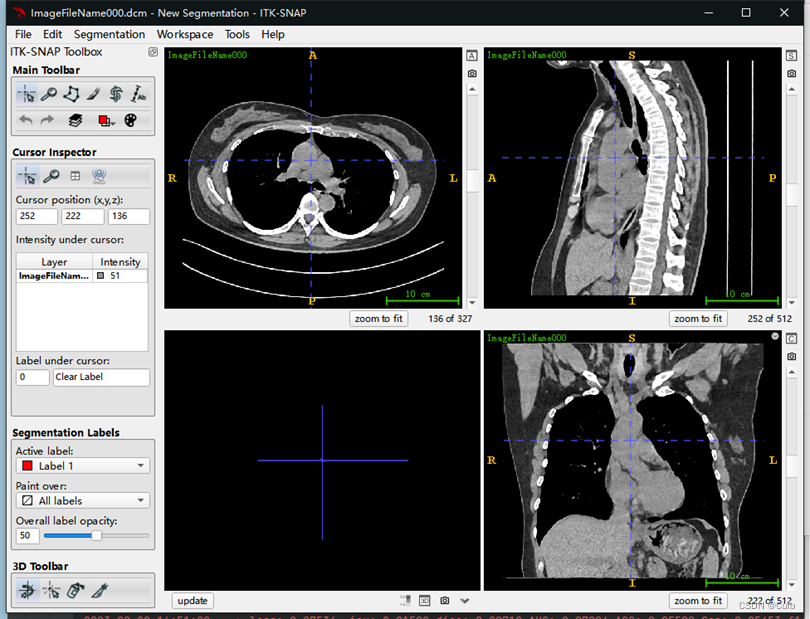

打开过后的效果如下

3 窗宽窗位调节

纵隔窗可观察心脏、大血管的位置,纵隔内淋巴结的大小,纵隔内肿块及这些结构的比邻关系。

纵隔窗:

窗位30 Hu~50 Hu;

窗宽300 Hu~500 Hu,

肺窗:

窗位-600 Hu ~ -800 Hu,

窗宽1300 Hu~1700 Hu,

在上述基本窗宽的基础上,若观察肺裂和肺血管,可调窄窗宽和调低窗位,对肿块形态,分叶,胸膜凹陷征,毛刺征增的观察肺窗比纵隔窗更为清晰。

先点击Tools,再点击Color Map Editor,出现以下画面,通过修改Level和Window来调节窗位和窗宽。这里根据以上参考,设置窗位为40,设置窗宽为400(可以发现心脏各部分的轮廓很清晰)。